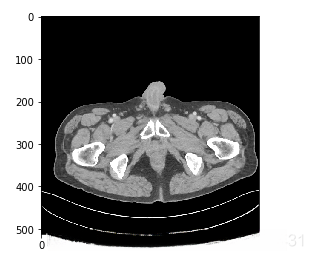

而在选取了窗宽窗位并对原图进行了clip之后的图是这样的:

是不是清晰了很多呢。